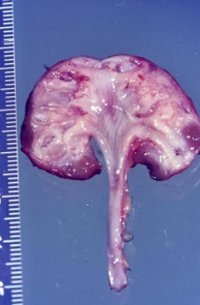

Es handelt sich pathologisch-anatomisch um eine kleine Niere mit einem Gewicht um 30g. Dabei sind die funktionellen Elemente (Renculi) numerisch reduziert auf 3 bis 5, normal 12 bis 14. Die Organanteile sind aber normal entwickelt (

Im Gegensatz zum in der Abbildung beschriebenen Beispiel besteht bei der Aplasie oder Dysplasie ein unvollständiges Gewebe mit erhaltenem fetalen Anteil (Abbildung 21).

Die echte Hypoplasie hat keine Komplikationen wie Hypertonie. Sie wird in der Regel zufällig entdeckt, im Gegensatz zur einseitigen pyelonephritischen Zwergniere mit Hypertonie. Die echte hypoplastische Niere ist selten. Zollinger fand unter 10.000 Obduktionen eine hypoplastische Niere. Die erworbenen Zwergnieren infolge entzündlicher oder vaskulärer Ursachen sind dagegen häufiger.